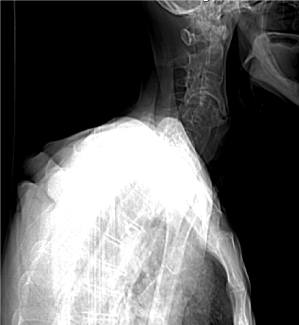

He was previously investigated before admission with a chest radiography, which came back normal. A barium swallow (Figures 1 and 2) was performed, which showed narrowing of the upper esophagus and gastro-esophageal reflux of contrast. An upper digestive endoscopy (UDE) found a tortuous esophagus presenting tertiary waves. An esophageal manometry was not able to be performed due to difficulty of catheter progression.

Figure 2. Barium Swallow: Gastroesophageal Reflux.